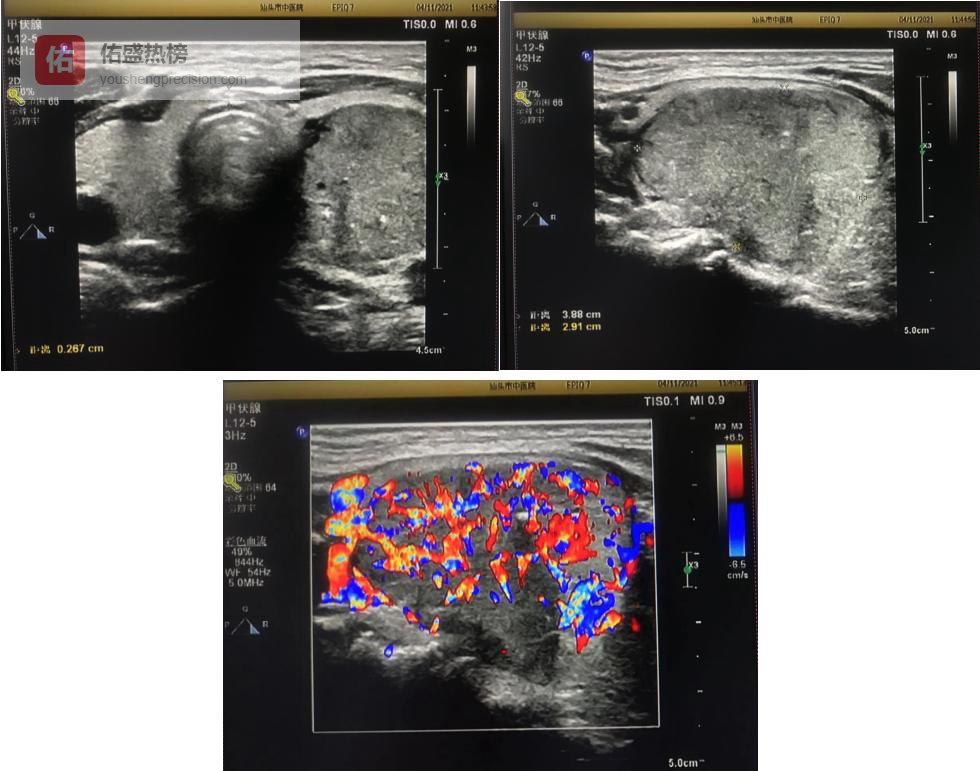

04一张图看懂“良恶性”超声暗号

恶性征象

实性低回声或极低回声

纵横比>1

分叶或边缘向周围浸润

粗钙化或砂粒体

癌转移淋巴结

形态趋圆、淋巴门消失

高回声团块伴钙化、囊性变

血流呈周围型或混合型